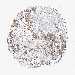

UROTHELIAL CANCER - Protein expressioni

A mouse-over function shows sample information and annotation data. Click on an image to view it in a full screen mode. Samples can be filtered based on level of antibody staining by selecting one or several of the following categories: high, medium, low and not detected. The assay and annotation is described here.

Note that samples used for immunohistochemistry by the Human Protein Atlas do not correspond to samples in the TCGA dataset.

Antibody stainingi

Antibody staining in the annotated cell types in the current human tissue is reported as not detected, low, medium, or high, based on conventional immunohistochemistry profiling in selected tissues. This score is based on the combination of the staining intensity and fraction of stained cells.

Each image is clickable and will lead to virtual microscopy that enables deeper exploration of all samples and also displays staining intensity scores, fraction scores and subcellular localization as well as patient and tissue information for each sample.

Antibody HPA029712

Antibody HPA029713

Staining

High

Medium

Low

Not detected

Intensity

Strong

Moderate

Weak

Negative

Quantity

>75%

75%-25%

<25%

None

Location

Nuclear

Cytoplasmic/membranous

Cytoplasmic/membranous,nuclear

Urothelial carcinoma, High grade